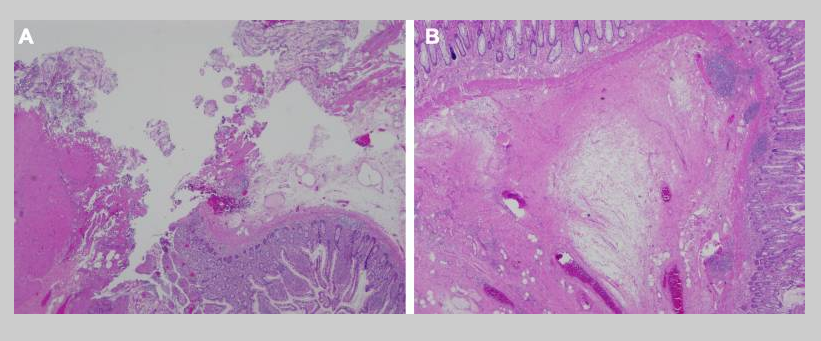

图3.狭窄回肠的组织病理。(A)肠壁中纤维蛋白沉积的缺损区域。(B)良性小肠组织,有粘膜下水肿和慢性炎症。未发现发育异常。